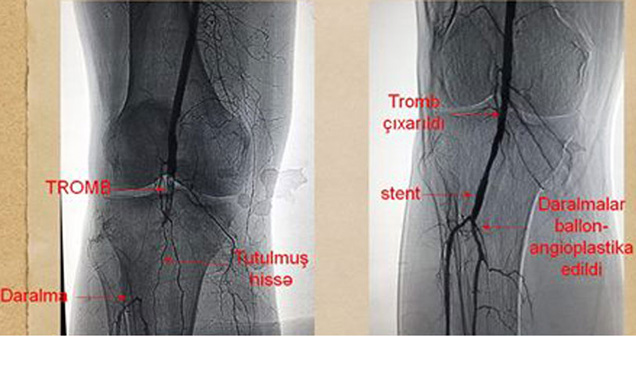

Şəkərli diabeti olan xəstələrdə yaralar sağalmırsa səbəbini araşdırmaq lazım və çox zaman əsas səbəb qan təchizatının yetməməsidir. Qan təchizatı düzəlmədikdə bu yaralar sağalmır və ayağın itirilməsinə gətirib çıxarır.Şəkərli diabet zamanı ayaqda sağalmayan yaralardan əziyyət çəkən xəstələr Avrasiya Hospitalın Diabetik Ayaq Mərkəzi-nə müraciət etmələri tövsiyə olunur. Diaqnostik angioqrafiya müayinəsi aparıldıqdan sonra İnvaziv yolla (qapalı üsulla) tromb çıxarılır, stent implantasiya edilir və ballon angioplastika edildikən sonra kontrol çəkilişlərdə normal axım izlənilir.Əməliyyatdan sonra ayaqda nəbz artıq hiss olunur və ilk saatlardan xəstənin ayağında ağrı keçərək rahatlama yaranır.Diabetik Ayaq Mərkəzinə müraciət etmək istəyənlər üçün: